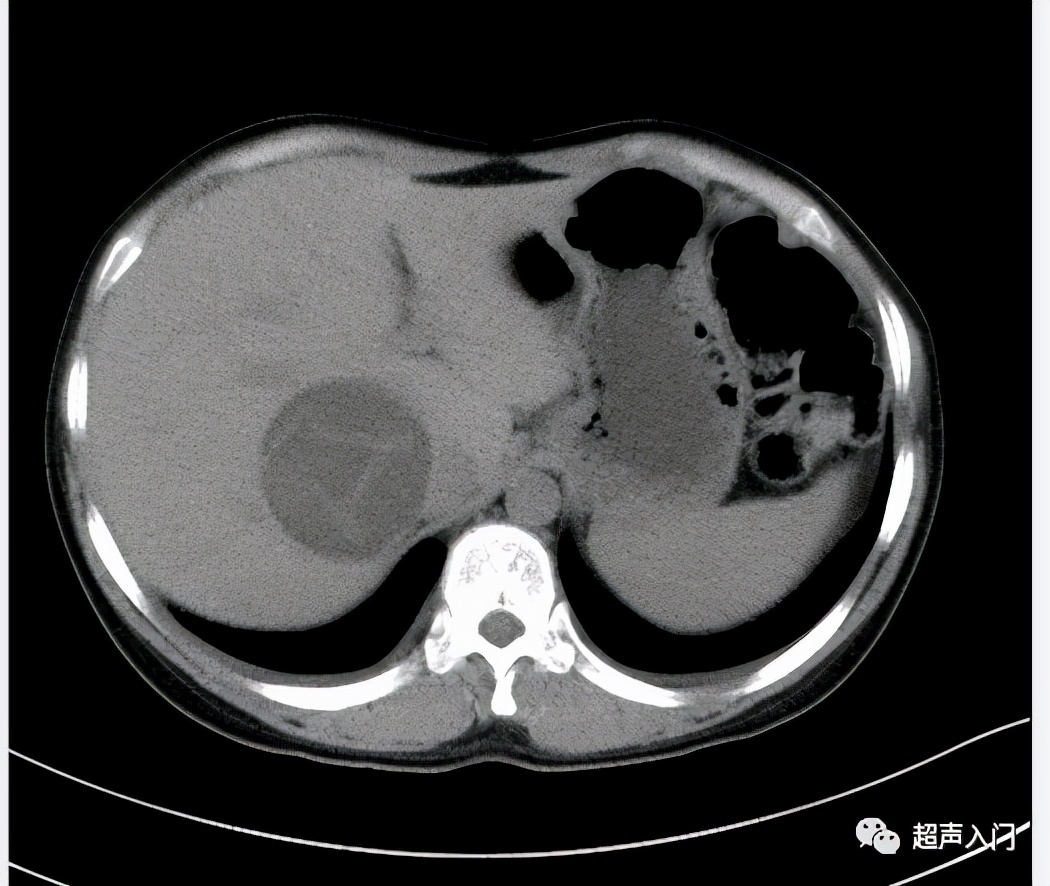

2、腹部增强CT和MRI:诊断价值很高,能显示囊肿与肝内结构的解剖关系,疑有胆道受累时,可行MRCP检查。

囊型棘球蚴病应与多囊肝、肝囊肿、肝脓肿等鉴别。

泡型棘球蚴病应与原发性肝细胞癌、结节性肝硬化、肺癌、脑肿瘤等鉴别。